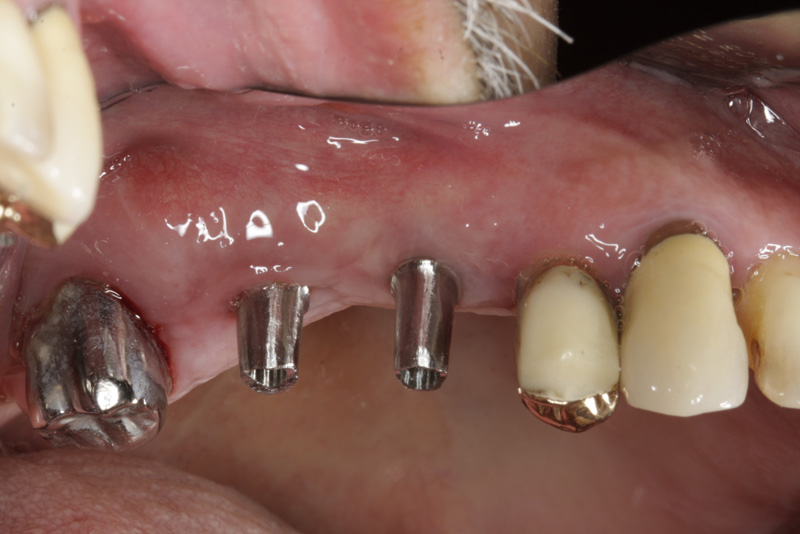

Protetické řešení může být pomocí můstku, který je kotvený na implantátech nebo pomocí jednotlivých korunek na implantátech.

V zásadě je možné do těchto můstků zařadit i přirozené zuby, zejména pokud je potřeba tyto zuby ošetřit proteticky

- korunkami. Korunky nebo můstky mohou být na implantáty nacementovány nebo přišroubovány.